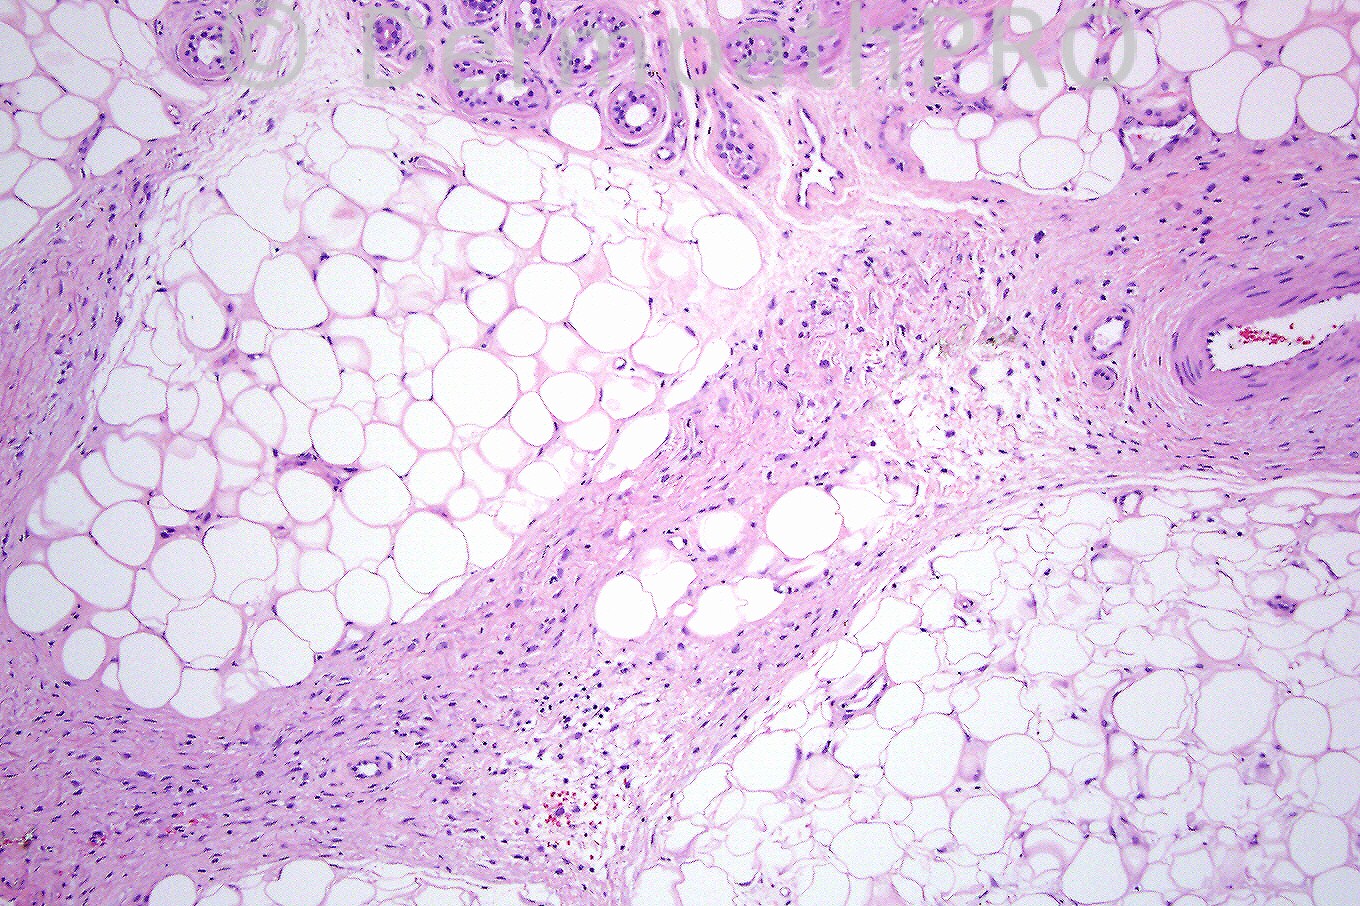

Patient with sclerotic lesions on limbs. Courtesy of Nooshin Brinster